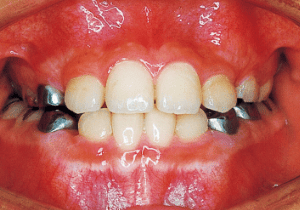

2 After treatment 2-10-’99

Although early treatment improved the slight deviation observed during the deciduous dentition stage, it became apparent that the deviation increased with age, eventually exceeding the limits of treatment. This appears to be an innate deviation, and the developmental pattern observed in this case seems to disregard the occlusion. Four first premolars were extracted (15), crowding was corrected and space closure was performed (16), and surgical intervention improved the deviation (17).